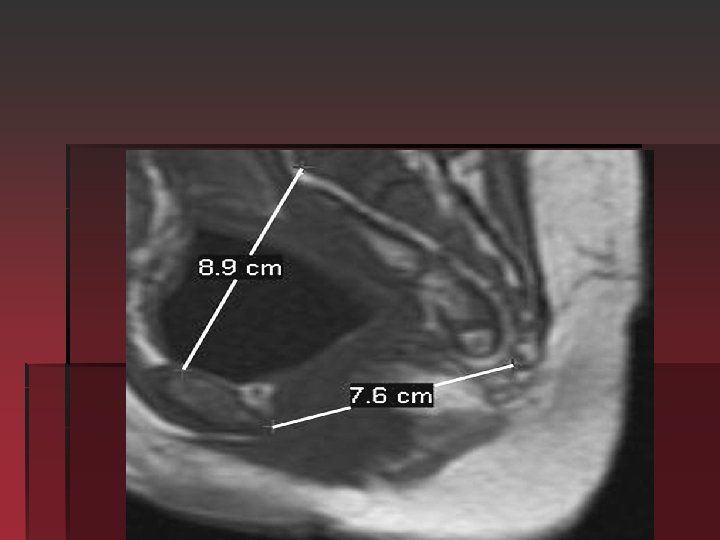

Radiological assessment of the pelvis: § When an accurate measurement of the pelvis is indicated nuclear magnetic resonance may be used. The advantage of MRI over the X-Ray or CT for the pelvic assessment is the lack of ionizing radiation exposure. Indications: 1 -Clinical evidence or obstetric history suggestive of pelvic abnormalities. 2 -Ahistory of pelvic trauma.